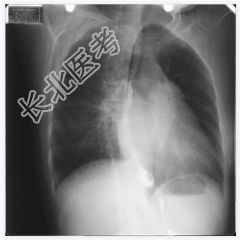

- [材料题] 女,50岁,主诉:胸闷、心悸4个月。听诊:心尖部听到舒张期和收缩期杂音。

- 简答题1、请问该案例诊断是什么?

- 简答题2、请问诊断依据是什么?

- 简答题3、风湿性心脏病临床表现有哪些?